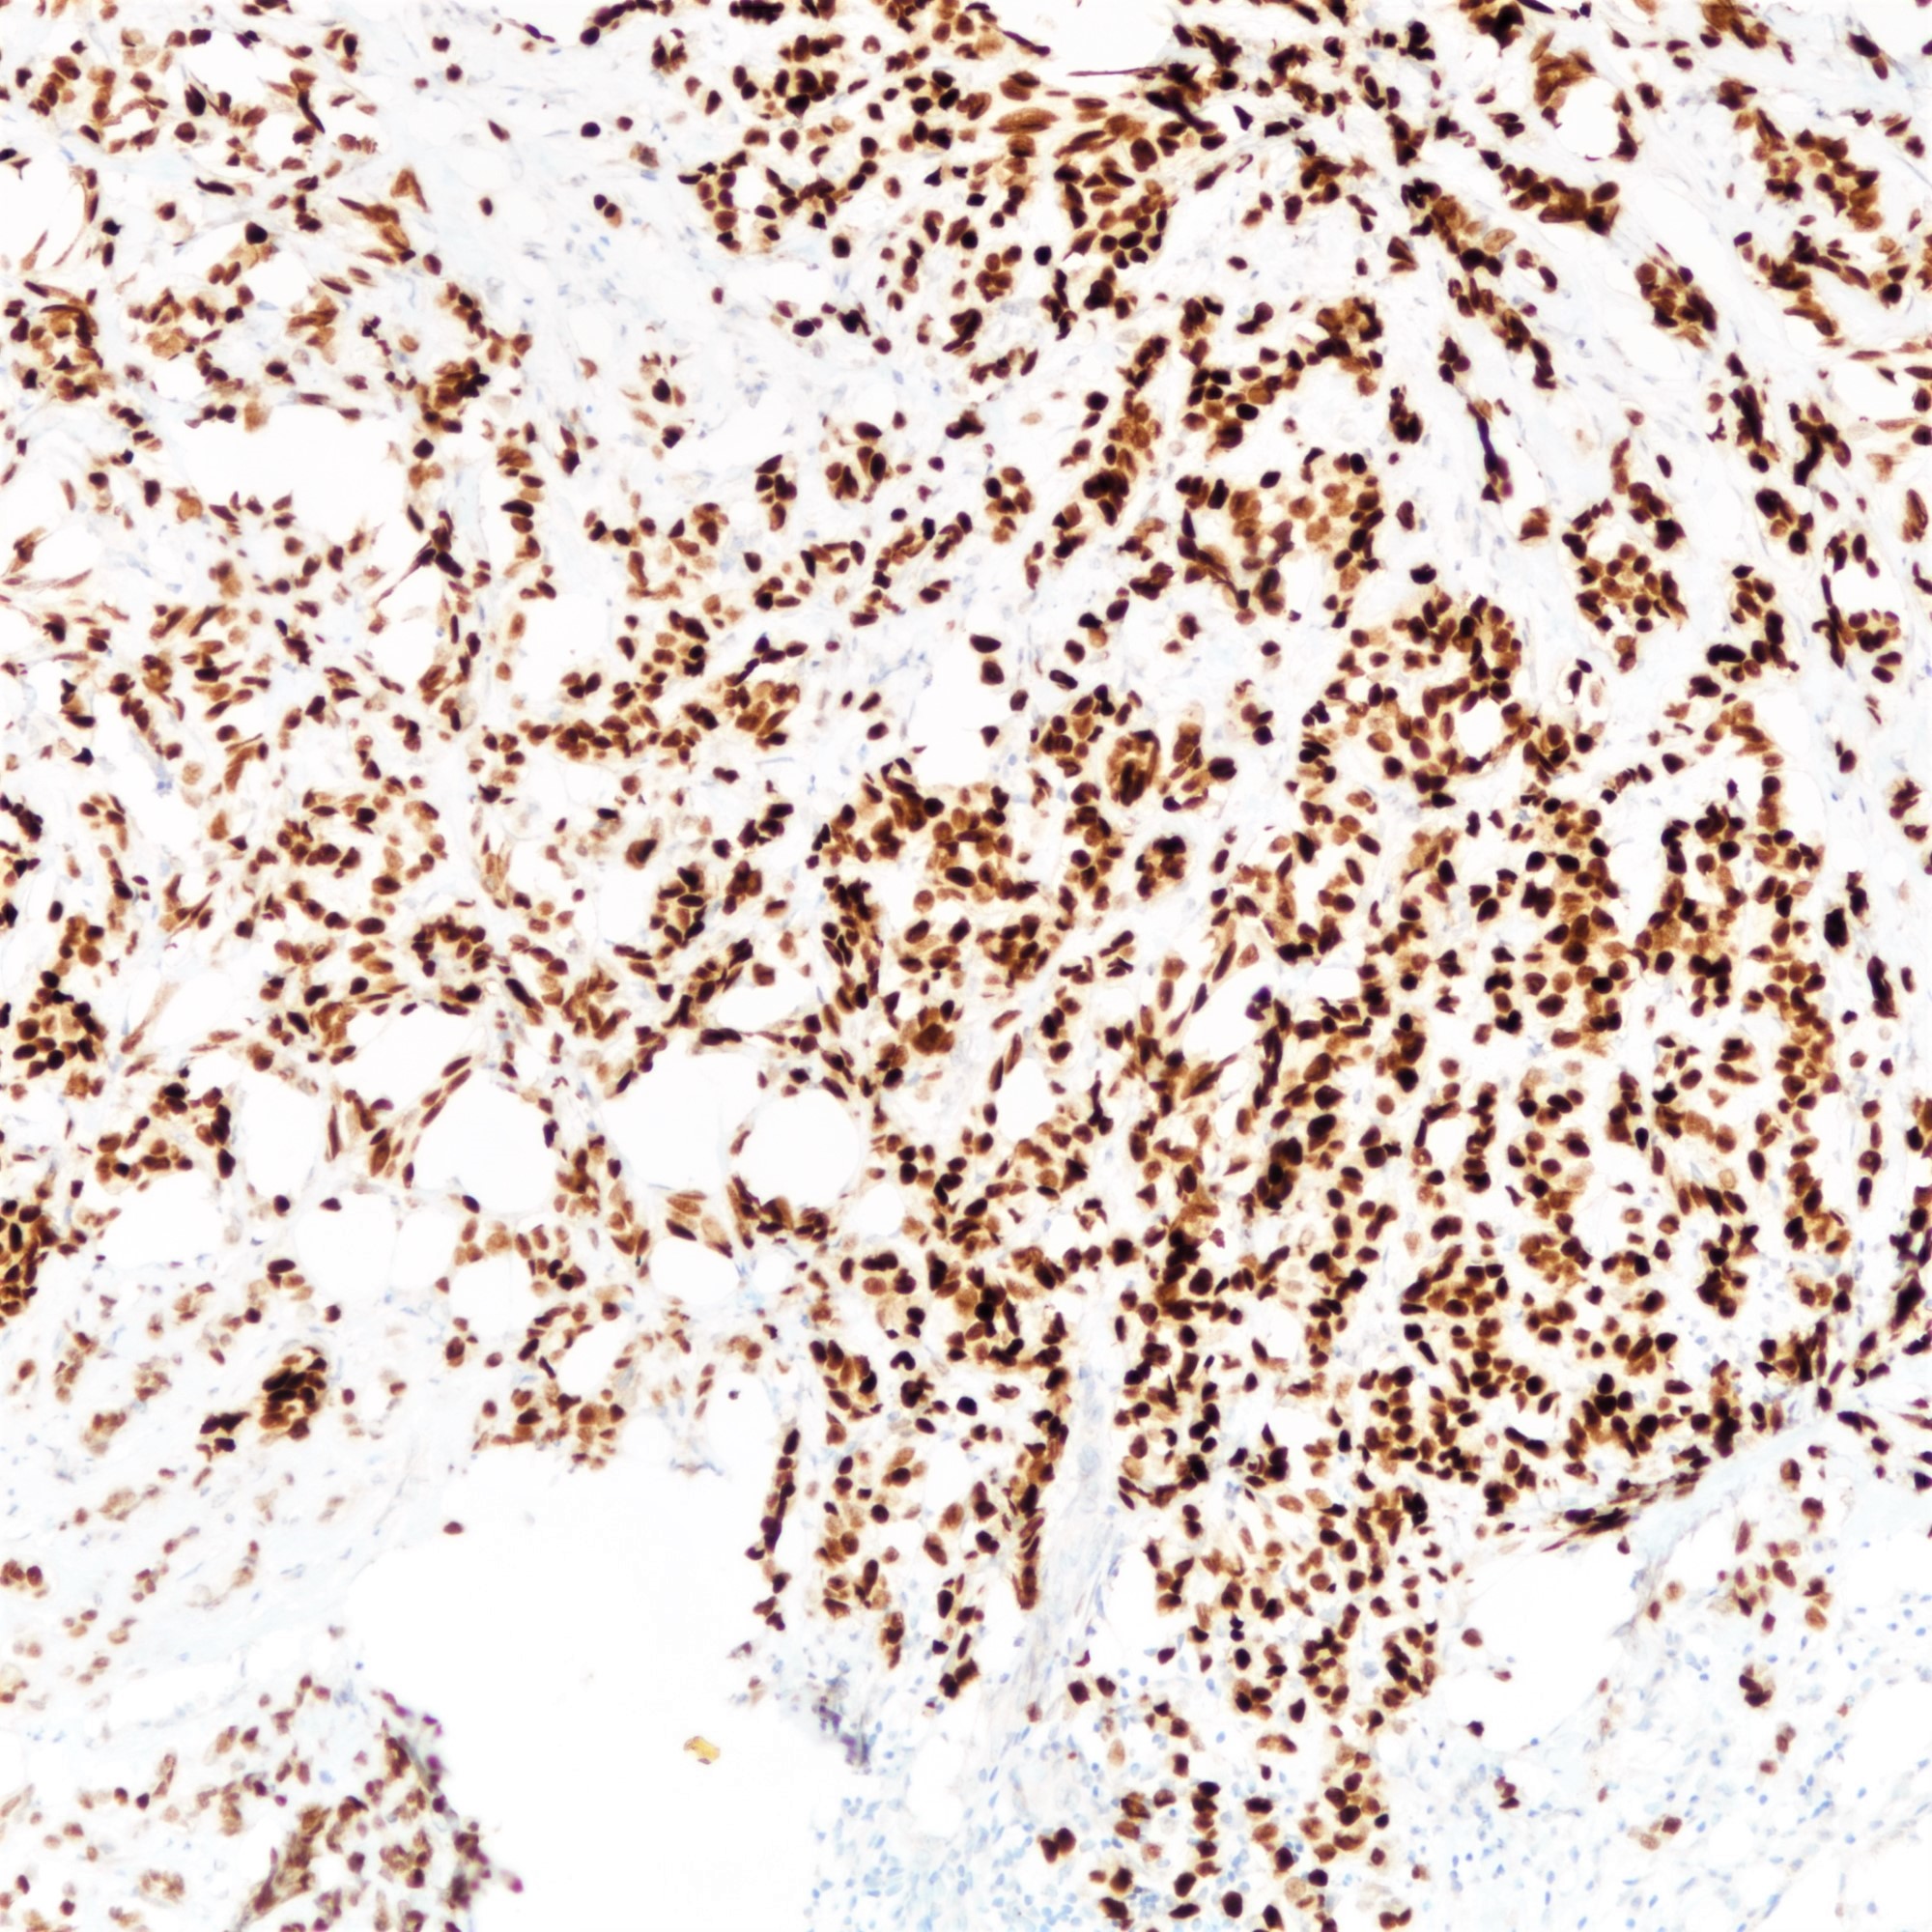

- Loss of E-cadherin expression on immunohistochemistry helpful but not required for diagnosis

- Majority of lobular carcinomas show loss of E-cadherin expression (Am J Surg Pathol 2010;34:1472)

- E-cadherin negative lobular carcinomas have a higher disease specific mortality than E-cadherin positive counterparts (Histopathology 2015;66:409)

Positive stains

Negative stains

- E-cadherin (16%) (Am J Surg Pathol 2010;34:1472, Hum Pathol 2020;102:44)

- E-cadherin absence or reduction of membranous staining, useful but not necessary for diagnosis of lobular carcinoma

- E-cadherin (16%) (Am J Surg Pathol 2010;34:1472, Hum Pathol 2020;102:44)